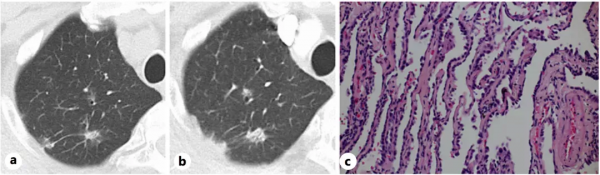

考慮A先生治療後疾病穩定,且隨訪其他部位沒有發生遠處轉移,醫生決定為A先生再次行手術治療,將病變的肋骨和肺部非浸潤性的病灶一併切除。對切除的病灶進行常規的病理檢查,醫生髮現A先生骨病灶上竟然沒有了存活的腫瘤細胞(圖2c、d),達到了病理學完全緩解(pCR);影像學上原有的病變(圖3a、b)被確證為非浸潤性腺癌(圖3c)。8天后,A先生出院了,沒有再接受包括奧希替尼治療在內的全身治療。

圖2. 肋骨轉移的影像學(a、b)、手術樣本(c)及病理染色(d)